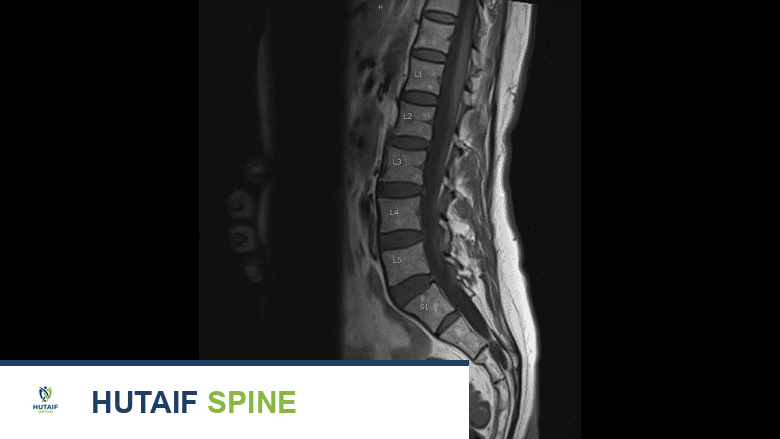

تصوير بالرنين المغناطيسي للعمود الفقري العلوي والسفلي

يُعد التصوير بالرنين المغناطيسي مفيدًا في الكشف عن انضغاط الأعصاب الشوكية أو الحبل الشوكي.

• التصوير بالرنين المغناطيسي (MRI): يستخدم التصوير بالرنين المغناطيسي (MRI) موجات الراديو ومغناطيسًا قويًا لإنشاء صور مقطعية للأنسجة الرخوة والعظام. يمكن أن يكون التصوير بالرنين المغناطيسي جيدًا بشكل خاص في الكشف عن انضغاط الأعصاب الشوكية أو الحبل الشوكي، الالتهابات، الأورام، أو تلف الأربطة، العضلات، أو الأنسجة الرخوة الأخرى.